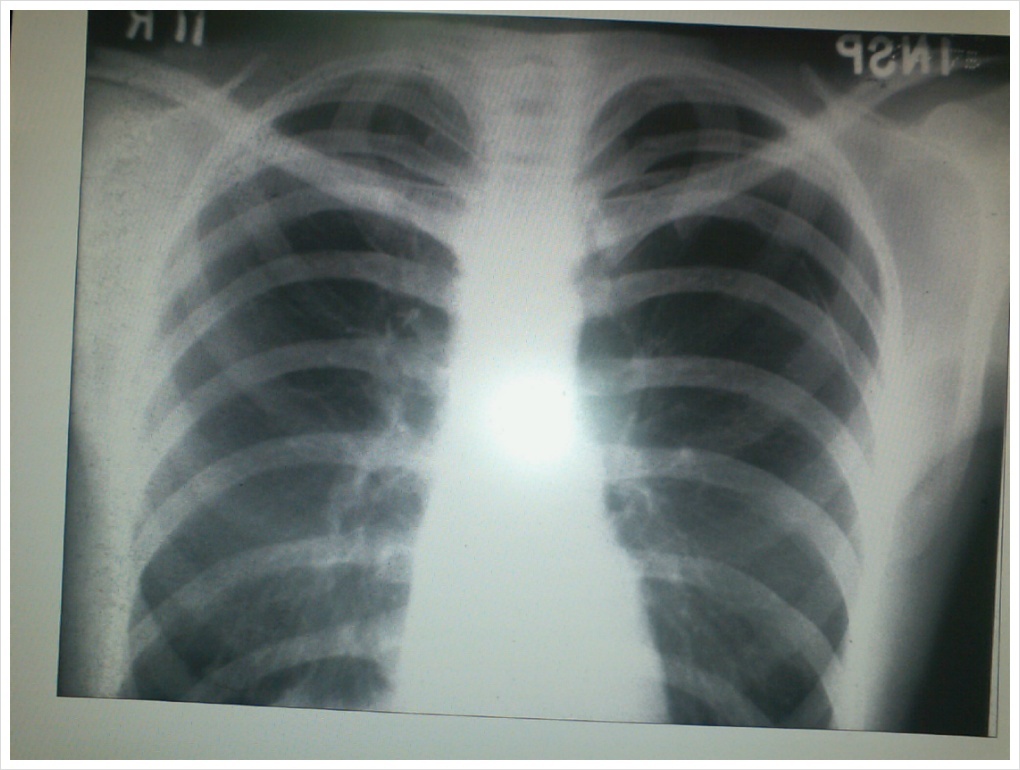

갈비뼈 골절

갈비뼈가 금이 갔을 때 대처 방법은 매우 중요합니다. 가장 우선적으로 해야 할 것은 병원에 방문해서 치료를 받는 것입니다. 금이 간 갈비뼈의 경우 진통제를 처방받거나, 기타 진료가 필요한 경우도 있습니다. 일단 병원 진료 후에는 절대 안정을 취하는 것이 가장 기본적인 대처 방법입니다. 온찜질을 하거나, 진통제를 꾸준히 복용하는 것도 통증을 완화하는 데 도움이 됩니다.

갈비뼈 골절은 부러진 것처럼 계속 아플 수 있으며, 약 한 달 정도 통증이 지속될 수 있습니다. 따라서 치료 과정에서는 인내와 주의가 필요합니다. 갈비뼈가 금이 간 경우에는 보통 진통제로 통증을 관리하면서 뼈가 붙기를 기다리는 방법이 주로 채택됩니다.